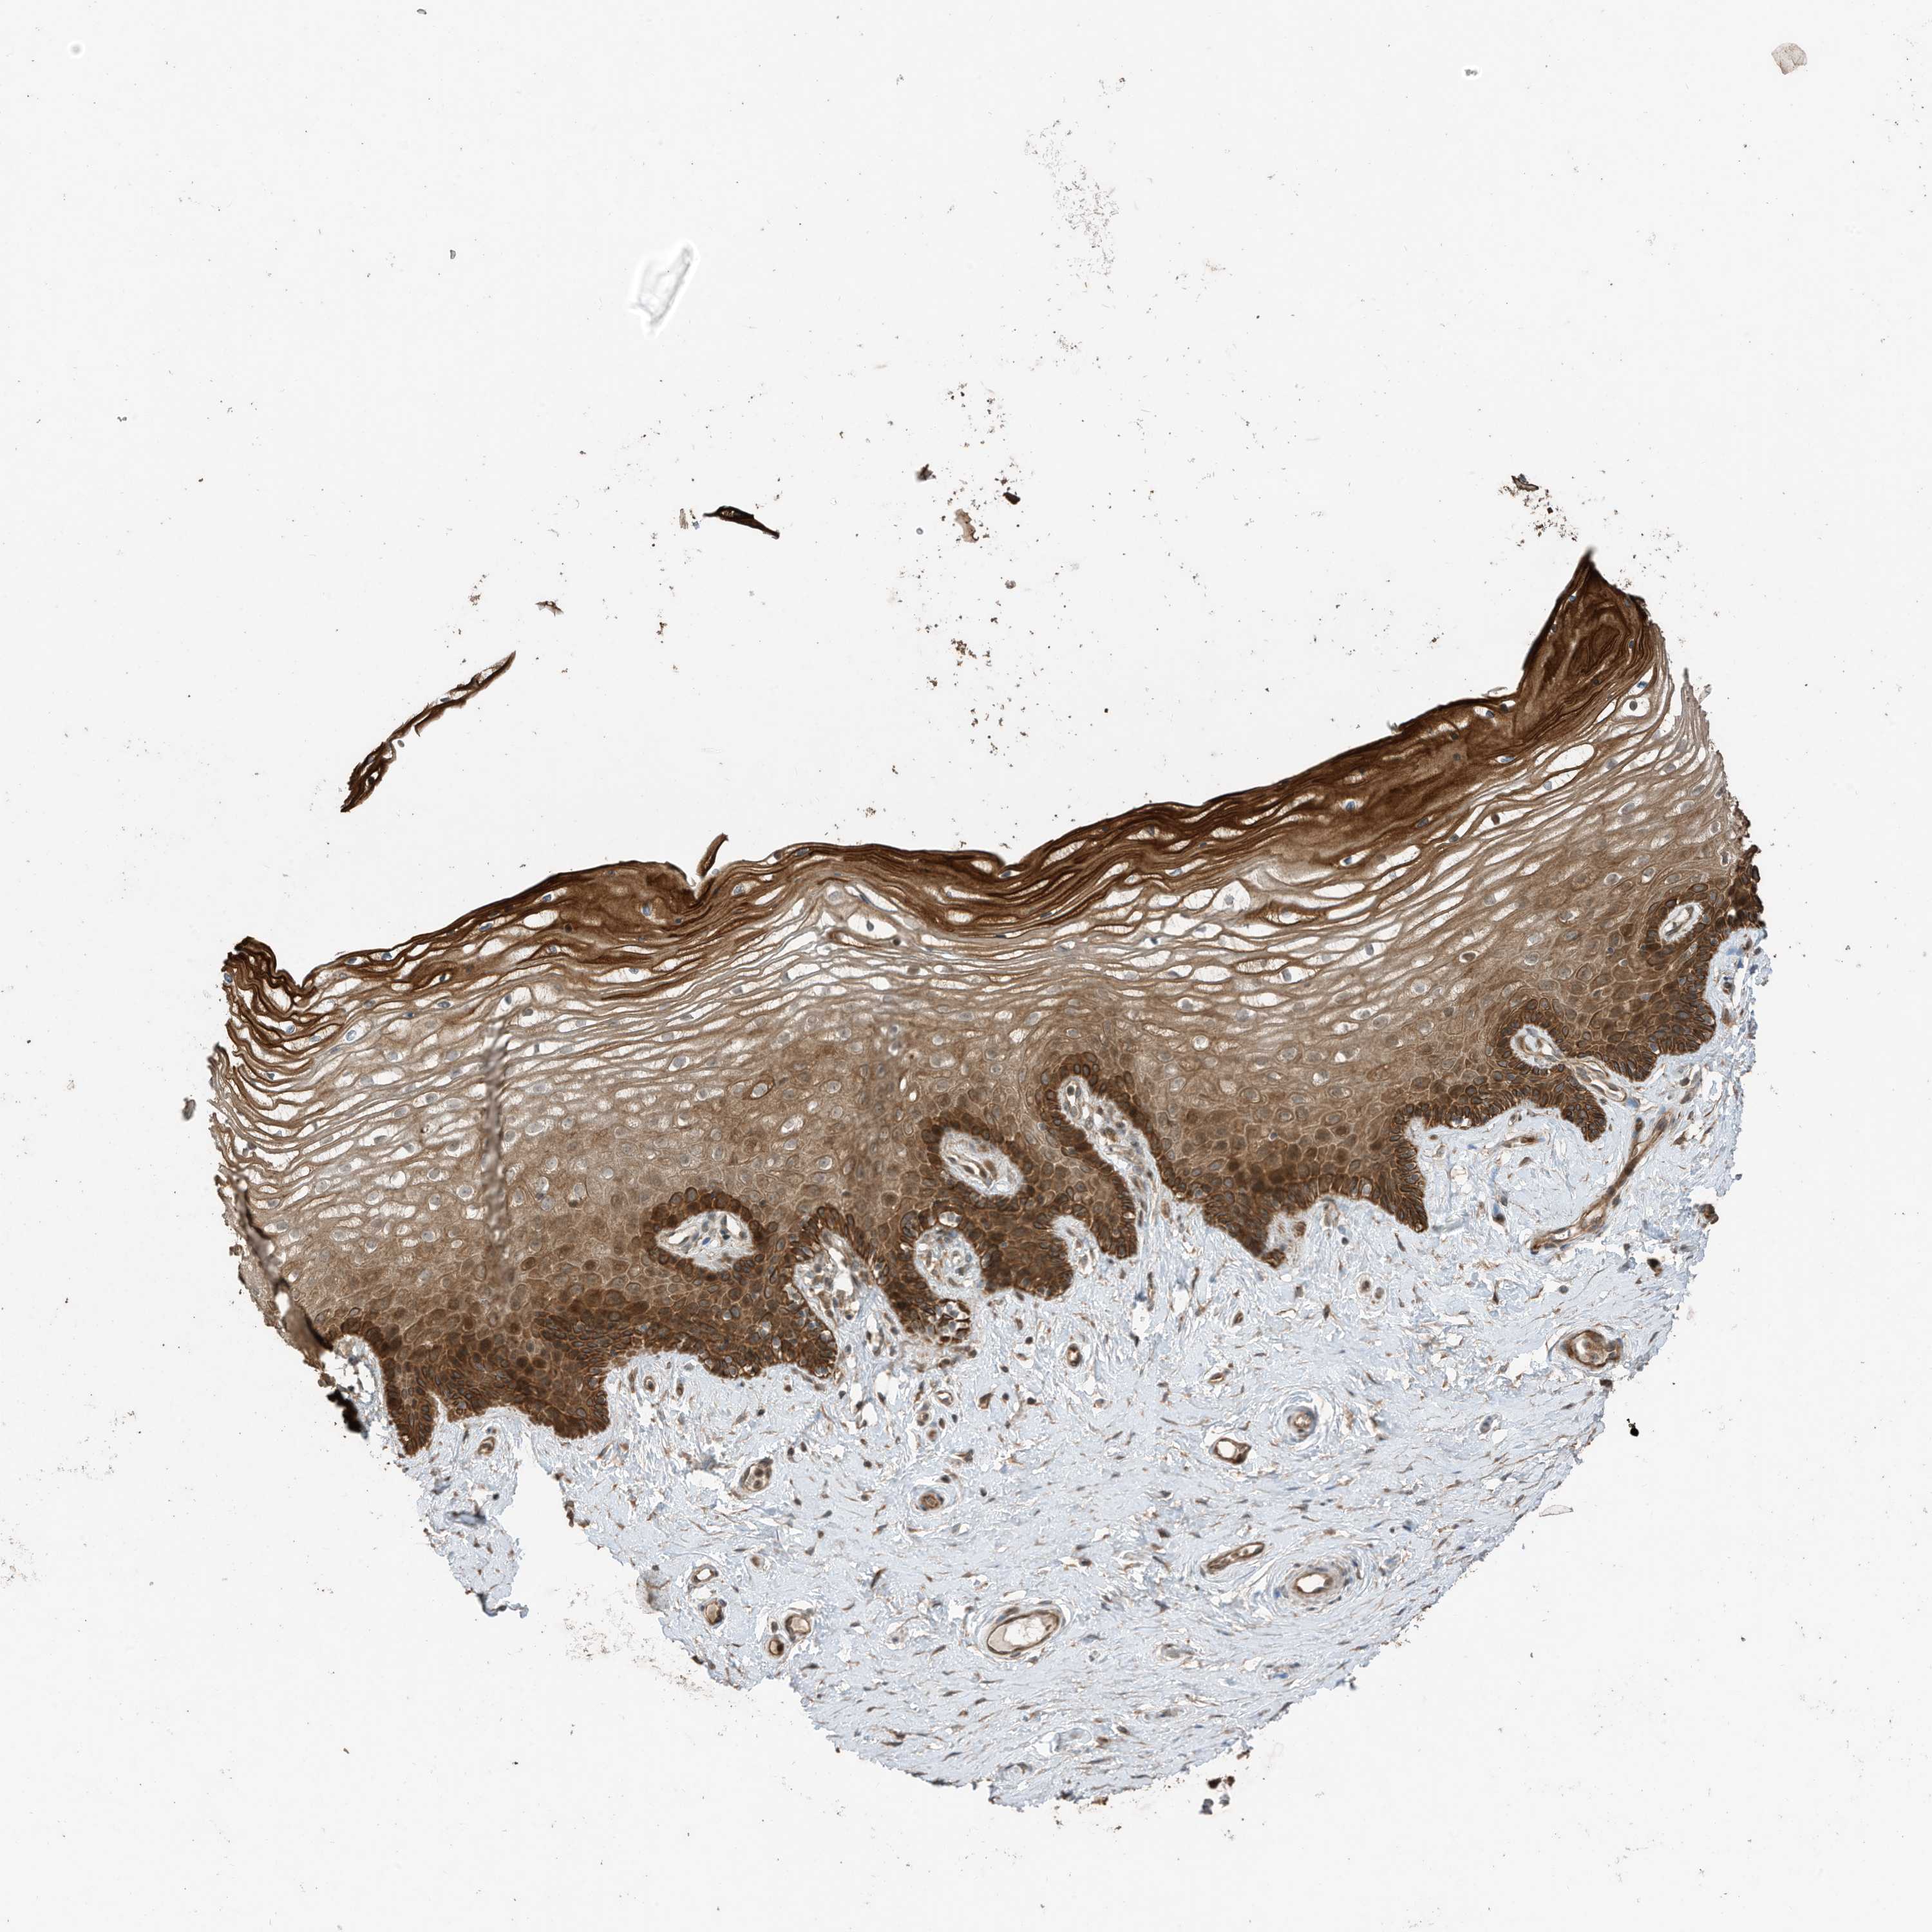

VAGINA - Antibody stainingi

Antibody staining in the annotated cell types in the current human tissue is reported as not detected, low, medium, or high, based on conventional immunohistochemistry profiling in selected tissues. This score is based on the combination of the staining intensity and fraction of stained cells.

Each image is clickable and will lead to virtual microscopy that enables deeper exploration of all samples and also displays staining intensity scores, fraction scores and subcellular localization as well as patient and tissue information for each sample.

Antibody HPA023631Antibody HPA023635

Squamous epithelial cells HighNot detected